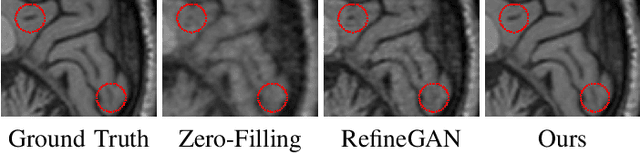

Abstract:Compressed Sensing Magnetic Resonance Imaging (CS-MRI) significantly accelerates MR data acquisition at a sampling rate much lower than the Nyquist criterion. A major challenge for CS-MRI lies in solving the severely ill-posed inverse problem to reconstruct aliasing-free MR images from the sparse k-space data. Conventional methods typically optimize an energy function, producing reconstruction of high quality, but their iterative numerical solvers unavoidably bring extremely slow processing. Recent data-driven techniques are able to provide fast restoration by either learning direct prediction to final reconstruction or plugging learned modules into the energy optimizer. Nevertheless, these data-driven predictors cannot guarantee the reconstruction following constraints underlying the regularizers of conventional methods so that the reliability of their reconstruction results are questionable. In this paper, we propose a converged deep framework assembling principled modules for CS-MRI that fuses learning strategy with the iterative solver of a conventional reconstruction energy. This framework embeds an optimal condition checking mechanism, fostering \emph{efficient} and \emph{reliable} reconstruction. We also apply the framework to two practical tasks, \emph{i.e.}, parallel imaging and reconstruction with Rician noise. Extensive experiments on both benchmark and manufacturer-testing images demonstrate that the proposed method reliably converges to the optimal solution more efficiently and accurately than the state-of-the-art in various scenarios.

Abstract:Magnetic Resonance Imaging (MRI) is one of the most dynamic and safe imaging techniques available for clinical applications. However, the rather slow speed of MRI acquisitions limits the patient throughput and potential indi cations. Compressive Sensing (CS) has proven to be an efficient technique for accelerating MRI acquisition. The most widely used CS-MRI model, founded on the premise of reconstructing an image from an incompletely filled k-space, leads to an ill-posed inverse problem. In the past years, lots of efforts have been made to efficiently optimize the CS-MRI model. Inspired by deep learning techniques, some preliminary works have tried to incorporate deep architectures into CS-MRI process. Unfortunately, the convergence issues (due to the experience-based networks) and the robustness (i.e., lack real-world noise modeling) of these deeply trained optimization methods are still missing. In this work, we develop a new paradigm to integrate designed numerical solvers and the data-driven architectures for CS-MRI. By introducing an optimal condition checking mechanism, we can successfully prove the convergence of our established deep CS-MRI optimization scheme. Furthermore, we explicitly formulate the Rician noise distributions within our framework and obtain an extended CS-MRI network to handle the real-world nosies in the MRI process. Extensive experimental results verify that the proposed paradigm outperforms the existing state-of-the-art techniques both in reconstruction accuracy and efficiency as well as robustness to noises in real scene.